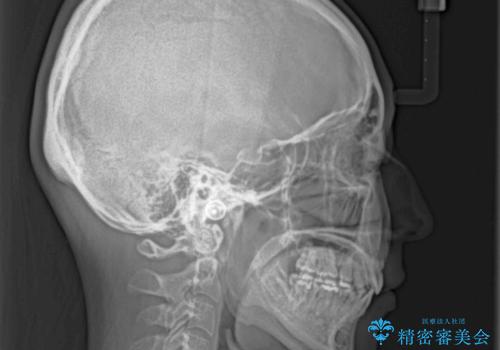

最終的には上下の正中も合い、横顔の印象が変わるほどスッキリとした口元となりました。